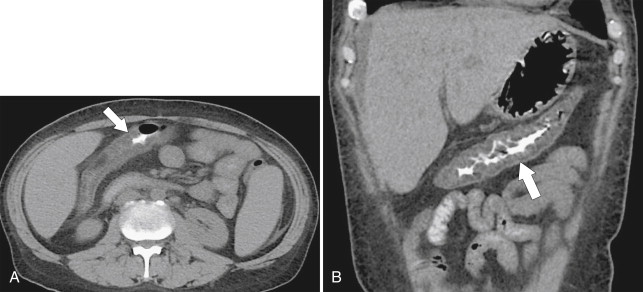

The presence and extent of disease are more readily evaluated by CT than by contrast enema, whose features also mirror the clinical disease. These include bowel wall thickening and luminal narrowing with a variable amount of pericolonic edema and mesenteric vascular hyperemia ( Fig. 5-13 ). The degree of inflammation may be reflected by 18 F-fluorodeoxyglucose (FDG) uptake at PET imaging ( Fig. 5-13 ). Mural stratification or double-halo sign, which is common with an acute presentation, is a nonspecific sign for inflammatory bowel disease representing hyperemic mucosa and serosa with intervening submucosal edema ( Fig. 5-14 ). If the acute disease worsens, the mucosa becomes progressively thickened and inflamed ( Fig. 5-15 ), which can ultimately lead to a toxic megacolon, whose CT features include a distended colon with profusely thickened mucosal tissue, sometimes referred to as an “accordion pattern” (see Fig. 5-52 ).

Figure 5-18, Axial ( A ) and coronal ( B ) contrast-enhanced CT in a 61-year-old woman with known ulcerative colitis and now an ascending colon adenocarcinoma ( arrows ) with associated lymphadenopathy ( small arrow ).